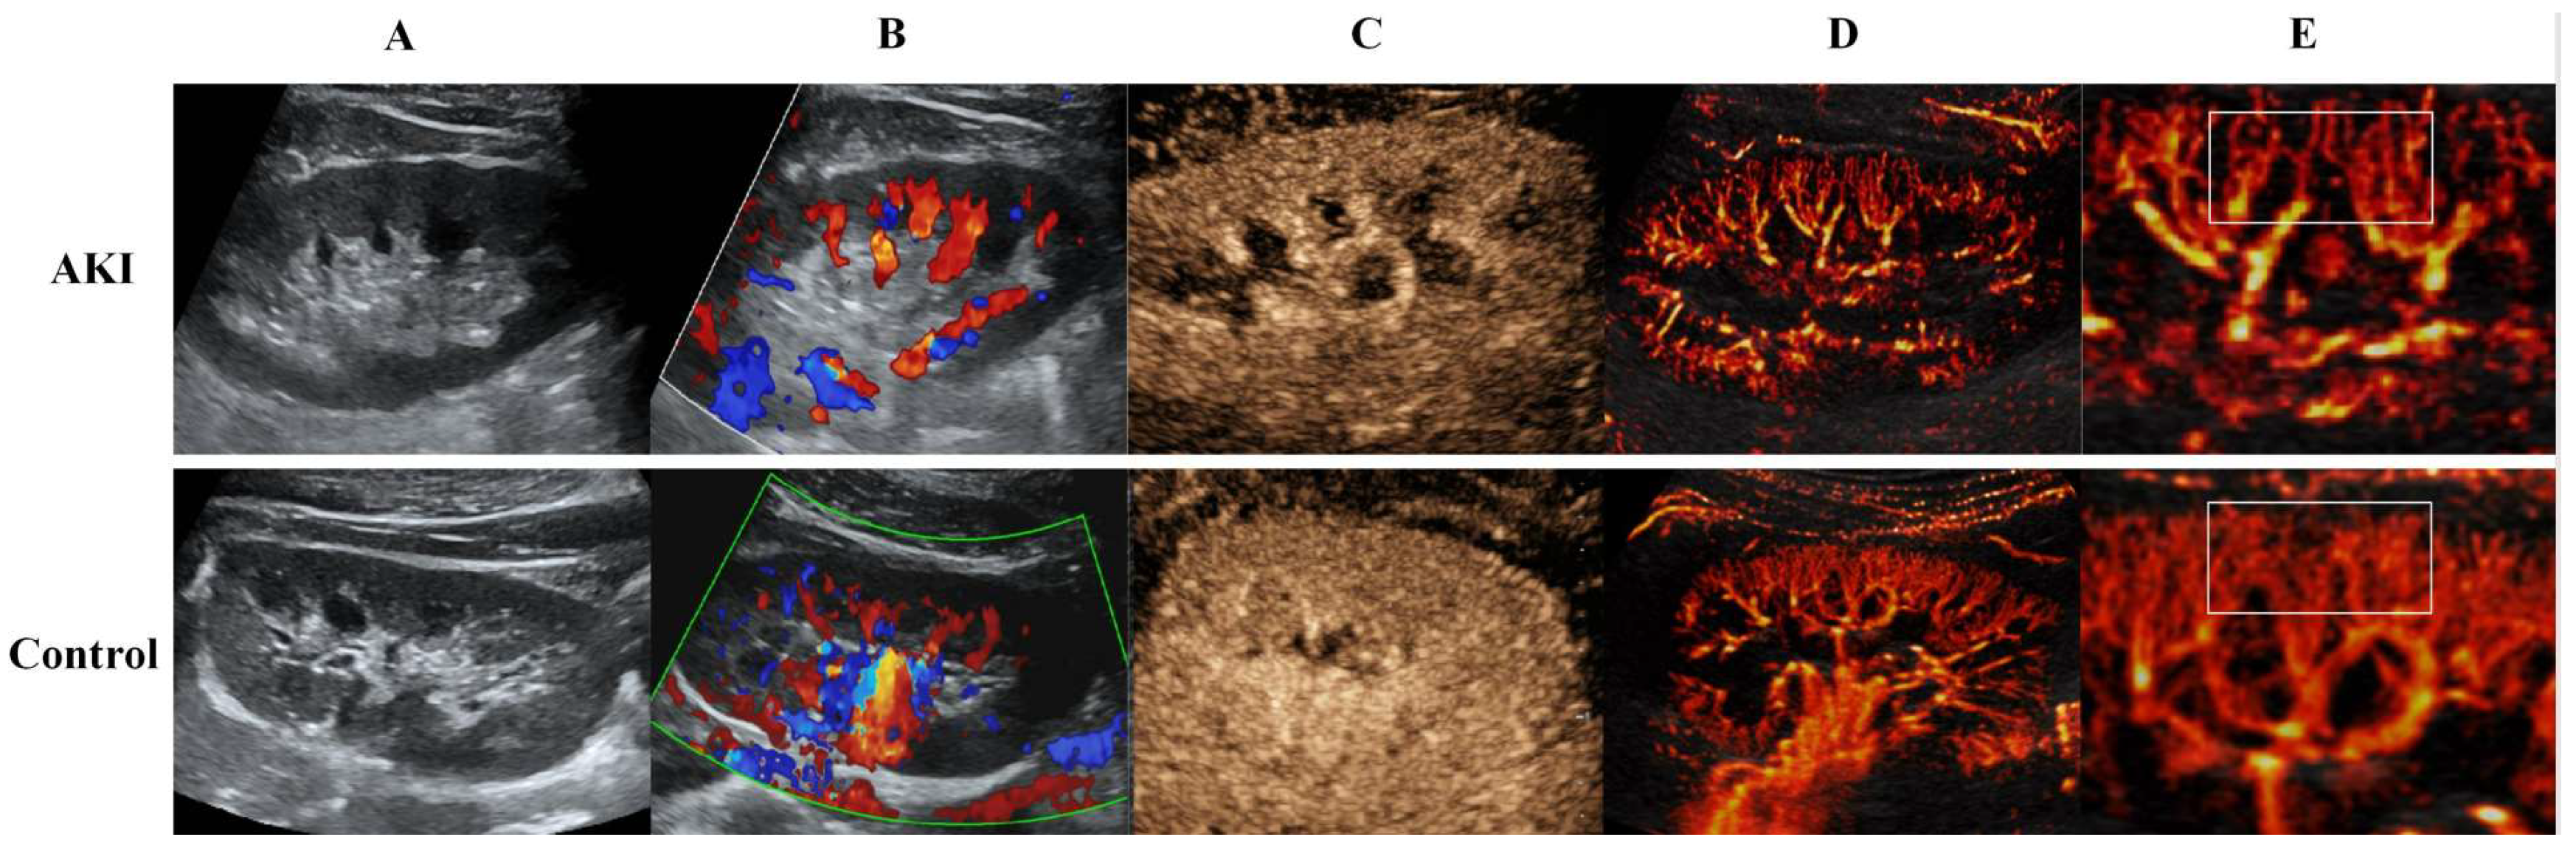

2.2. US Image Acquisition

2.3. CEUS Image Acquisition

2.4. US SRI Acquisition